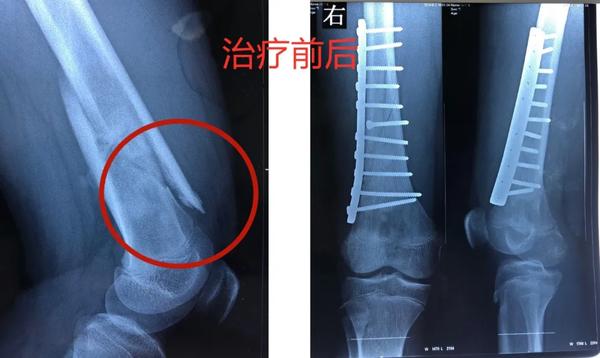

12歲的男孩兒浩浩,在學校上體育課,扭傷后突發(fā)右側大腿劇烈疼痛,不能活動,被家人緊急送到醫(yī)院,當?shù)蒯t(yī)院拍片后提示右股骨中下段斜行骨折。隨后,醫(yī)院按照一般骨折處理。

當?shù)蒯t(yī)生將病理組織送河南省腫瘤醫(yī)院病理會診,提示為骨肉瘤。消息猶如晴天霹靂,但更讓兩個孩子的父母痛苦的是,“由于按一般骨折做了手術、打了鋼板和鋼釘,破壞了腫瘤外面原本相對完整的包膜,這個自然屏障一旦被破壞,腫瘤細胞就會‘污染’周圍組織,以后想再切干凈就更困難了。”河南省腫瘤醫(yī)院骨與軟組織科主任、主任醫(yī)師姚偉濤表示。

身體異常:排除感冒、發(fā)燒引起的,患者出現(xiàn)持續(xù)發(fā)熱,并伴有體重下降,活動能力下降,且有難以解釋的持續(xù)性疼痛。骨折:腫瘤持續(xù)“破壞蠶食”骨質(zhì),最后就像浩浩和晨晨一樣,輕微的外力下就會發(fā)生一處甚至多處骨折。揪出骨肉瘤 核磁是關鍵那怎么才能確診骨肉瘤呢?檢查骨肉瘤首先要拍X片,其次是磁共振,最終要依靠活組織檢查來確診。一定不能忽視磁共振檢查。王鑫提醒道:骨肉瘤就像一個表面看起來很小的水坑,實際上坑里的水已經(jīng)向周圍浸潤了很大一片。在X光片上僅能看到很小的一個病灶,而在磁共振上,可以判斷腫瘤的實際大小和確切范圍,減少誤診漏診。就像浩浩、晨晨這樣,以為只是骨折,拍了片子,即使看出有一些異常,也可能沒在意,這樣打鋼板、鋼釘,弄破了瘤子后期治療就不好進行了。磁共振不僅對確診有幫助,而且對治療也有指導作用。“手術時要在腫瘤周圍正常組織內(nèi)切除腫瘤,保證腫瘤的邊界干凈,才能提高治愈效果。”王鑫解釋說。

最終,王鑫醫(yī)師組為浩浩、晨晨兩位小朋友選擇了新輔助化療,待疼痛癥狀緩解后,手術取出鋼板、鋼釘,并通過擴大切除手術,完整切除長瘤子部分的股骨,并進行體外滅活,搭配腫瘤型組配人工膝關節(jié)置換,達到了既完整切除腫瘤,又保全了孩子肢體功能的目的。做到這些讓孩子遠離骨肉瘤骨肉瘤的致病原因目前并不明確,常認為是多種因素綜合導致,比如放射性輻射、接觸化學物質(zhì)、基因突變等。首先,家長對于孩子出現(xiàn)身體異常,一定要引起重視,發(fā)現(xiàn)子女在不明確病因的情況下出現(xiàn)了骨頭疼痛、關節(jié)腫痛,請及時前往醫(yī)院查明病因;家長要多鼓勵孩子外出進行戶外運動,不要接觸過多放射性輻射;另外,戶外運動時,也要注意關節(jié)處的保護,提醒孩子注意運動秩序和方式,避免造成骨骼損傷及軟組織拉傷。王鑫提醒,如果出現(xiàn)問題,懷疑骨腫瘤性疾病,尤其是合并病理性骨折,家長一定要帶孩子到專業(yè)的骨腫瘤科就診,必要時行磁共振檢查,仔細甄別骨折原因!